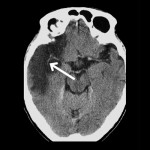

Compared to the previous CT scan, the films shown here is from a patient with a chronic right middle cerebral artery territory infarct

(Figures 1 and 2). There is a sharply delineated wedge-shaped hypodense area (approaching the density of cerebral-spinal fluid) involving the grey and white matter supplied by the right middle cerebral artery.